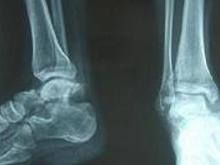

♥距骨骨折脱位

大多系高处坠下时的压缩或挤压暴力所致,尤以足背伸时更易引起此时以距骨颈部骨折为多发次为距骨体骨折足处于中间位时多导致距骨体骨折[1]而足跖曲时则距骨后突骨折多见类同的暴力尚可引起距骨的脱位。